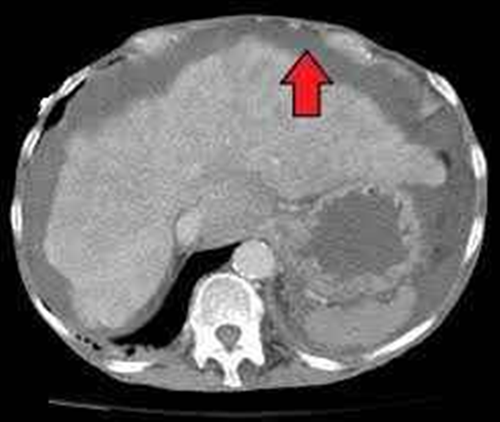

말기 담도암에서 복수의 진단은 신체검사와 CT 스캔, 초음파 등의 영상 검사를 통해 이루어집니다. 신체 검사 중에 의사는 간 비대, 림프절 부기 또는 복부 비대를 느낄 수 있습니다. 영상 검사는 복수의 존재를 확인하는 데 도움이 될 수 있으며 복수의 원인을 파악하는 데도 도움이 될 수 있습니다.